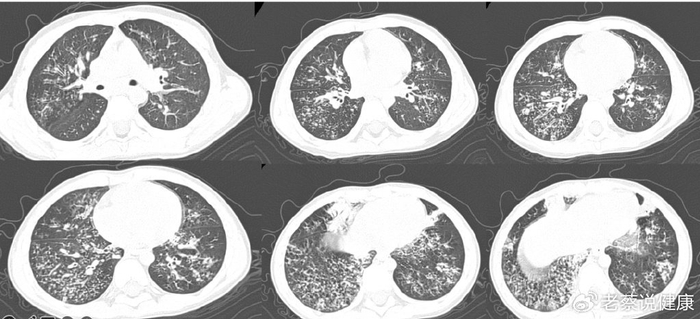

支原体肺炎该有的 ct 特点,这个患者都有了_临床_病例_检查

支原体肺炎之早期影像特点